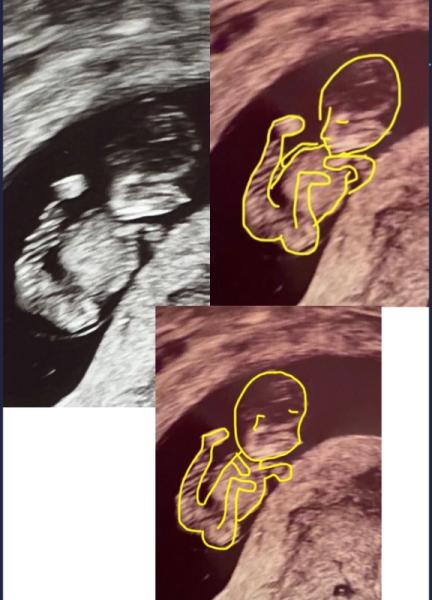

Hier mal ein us Bild von meiner 3. Ss in der 11. Woche, da erkennt man was ich meine. Riesiger Bauch und Kopf und winzige Arme und Beine

Bild zu